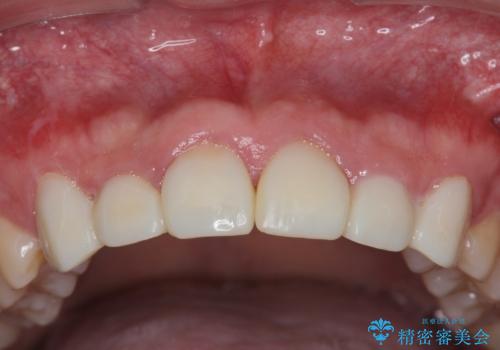

歯周外科を行い、歯ぐきの状態を整えた前歯セラミック治療

- 「前歯の見た目、歯ぐきの腫れを改善したい。」と希望され来院されました。

前歯には接着性の維持装置や、中途半端な形の連結クラウンが装着され、清掃性が悪く歯ぐきの腫れや、歯ぐきの形態の不揃いが認められました。

歯周外科を行ったことで、歯ぐきの形態や腫れが改善され、審美性だけでなく清掃性も大きく改善することができました。